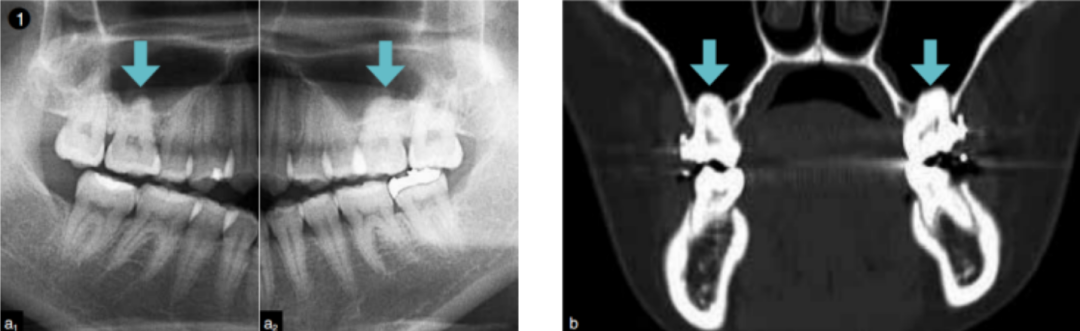

上颌窦底低,会有在X线片上看到上颌磨牙牙根突入上颌窦内的情况图1。实际上这不是牙根突出在上颌窦内,而是有一层像纸一样薄的骨存在在牙根周围,但拔牙的时候可能会连这一层薄骨和牙根一起拔除,这就会造成穿孔。

图1 向上颌窦内突出的牙根。拔牙的话,穿孔的可能性较高